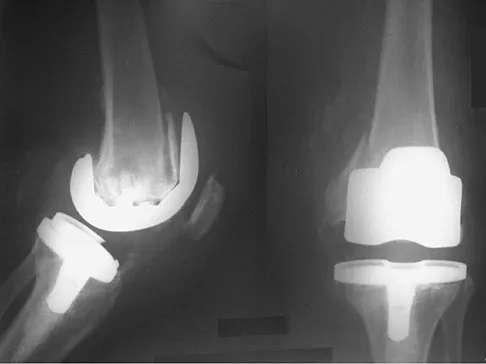

Figures 5a and 5b show the radiographs of an active 52-year-old man who has increasing knee pain and progressive varus deformity after undergoing total knee arthroplasty 7 years ago. Examination reveals a small effusion, but he has good motion and stability. What is the most likely diagnosis?

Detailed Explanation

The radiographs show narrowing of the medial joint space, which indicates polyethylene wear and progressive varus alignment. Wear particles incite osteolytic lesions like the one seen on the lateral radiograph. O'Rourke MR, Callaghan JJ, Goetz DG, et al: Osteolysis associated with a cemented modular posterior-cruciate-substituting total knee design. J Bone Joint Surg Am 2002;84:1362-1371.